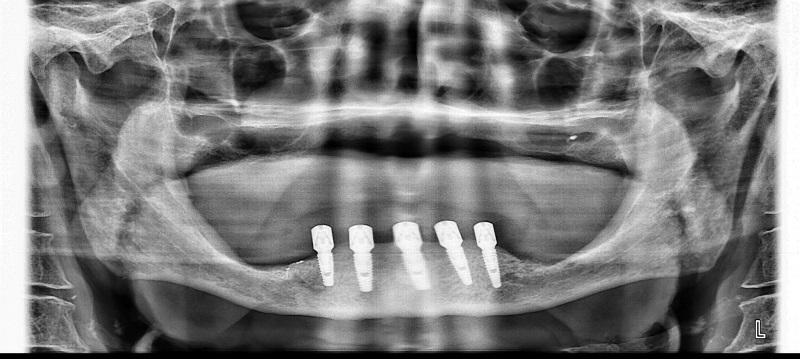

Рентген имплантов Alpha Bio: диагностика и качество